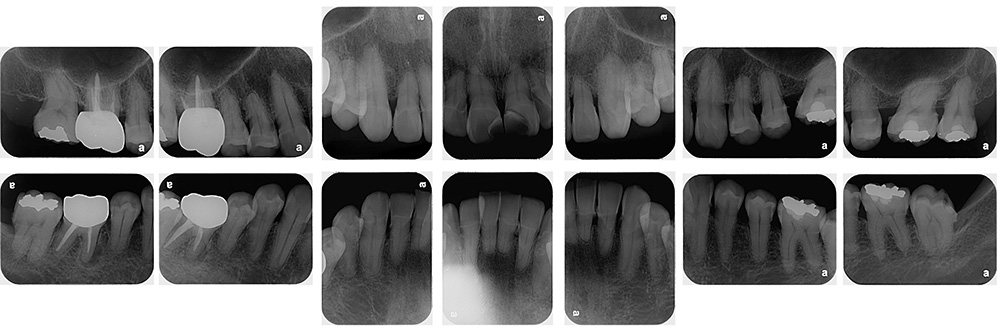

術前

術後

世代・性別

40代女性

主訴

歯が揺れている気がするので見てほしい

治療内容

ブラッシング指導、歯周基本治療

治療期間

4ヶ月

治療費

保険適応内

治療のリスク

一時的に歯ぐきからの出血や痛み、歯のしみ(知覚過敏)が起こることがある